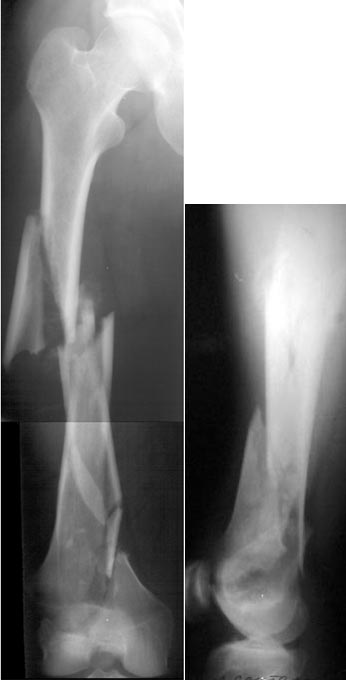

of course the only radiograms both the view of the femur (AP and LL) are not enough in order to assess the condilar ones.

So I think a TAC of the knee could be useful.

If You're going to use a nail,it could be blocked proximally and distally,because of the spiroid rime of the fracture.

But,in my opinion,the real problem is the distal fracture and so I suggest the use of a long plate,long until the condilars

The best healing is anticipated if the fracture site is not opened (virtually the whole thigh in your tough case!).

I tried to think of LISS, but it would be difficult to perform after a month (no fracture hematoma but there is fibrosus callus formation). And even the longest LISS would be short here, not to mention the very small distal piece.

Attempt to apply external fixator and perform reduction and provisional fixation by wires, then antegrade closed nailing.

consider retrograde IM nail with distal fragment screw fixation as needed

Distal articular reduction /fixation with retrograde IM nail or long LISS plate.

Мы пошли на операцию с планом попытаться сделать закрытый интрамедулярный, а не получится - сделать аппаратом. Посчитали, что получилось, хотя на еженедельной конференции ожидаются некоторые проблемы с объяснениями ;-)

Насчет стабильности для ранней нагрузки, конечно, сомнительно, но при таком повреждении ранняя нагрузка противопоказана в любом случае. Для ранних движений Должно хватить. Снимки в следующем сообщении.